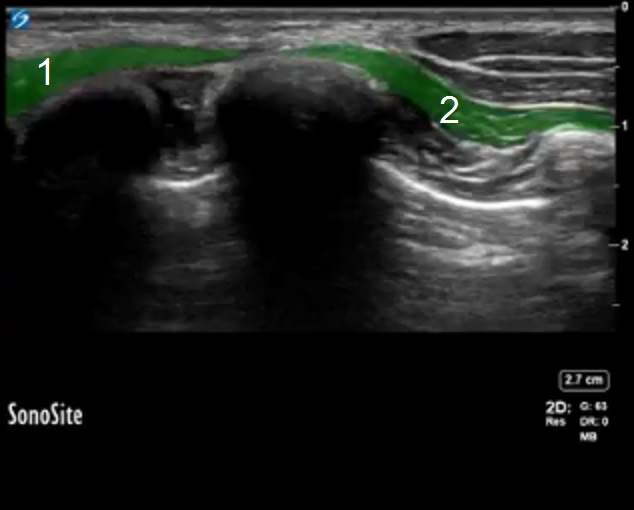

Bild 2: Serratus- und Latissimusmuskel

Musculus latissimus dorsi

Musculus serratus anterior